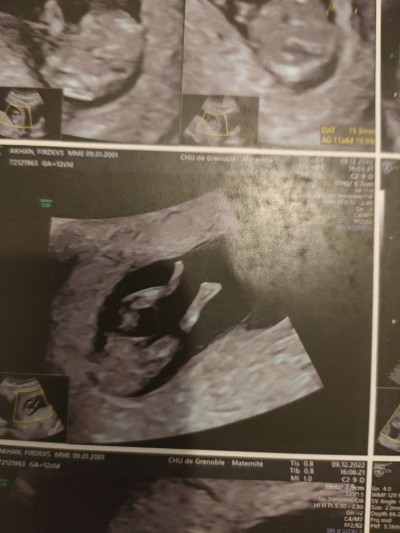

Kızlar bugün doktara gitim cinsiyet tahmini yaparmısınız doktor birşey söylemedi çok merak ediyorum

Gebelik haftası 12+1

neden tahmin de bulunmadı acaba bacak arası boş küçük çıkıntı var oda içe doğru yani kiz bence  haftanız küçük diye demedi demek ki birsey

Ben erkeğe benzettim. Sağlıkla kucağınıza alın.